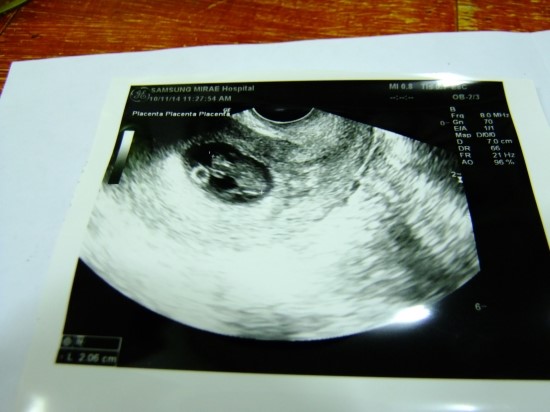

[8주 4일] 뚝심이 심장소리, 기차소리, 말발굽소리?ㅋㅋ

2014년 10월 11일, 8주 4일, 두번째 정기 검진일! 이주만에 돌아온 병...